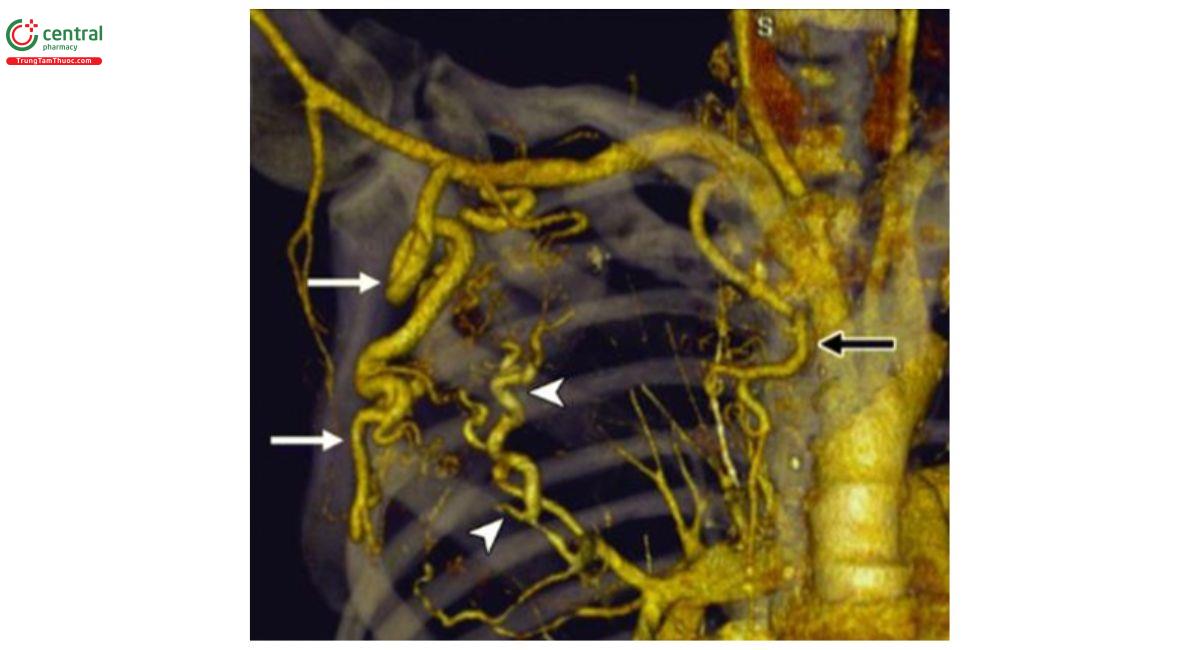

5.4 Lập bảng đồ mạch máu

CLVT mạch máu có thể đánh giá chi tiết và chính xác bản đồ mạch máu lồng ngực và hướng dẫn cho các phương thức điều trị tiếp theo. Một vài nghiên cứu chứng minh CLVT mạch máu với tái tạo đa mặt cắt cũng cho kết quả chi tiết và chính xác hơn chụp mạch máu xóa nền trong việc xác định gốc và sự phân nhánh của ĐMPQ cũng như ĐMHTKPQ.

![Hình 3. Hình chụp VRT mạch máu giúp xác định gốc động mạch phế quản [8].](/images/item/ho-ra-mau-3.jpg)